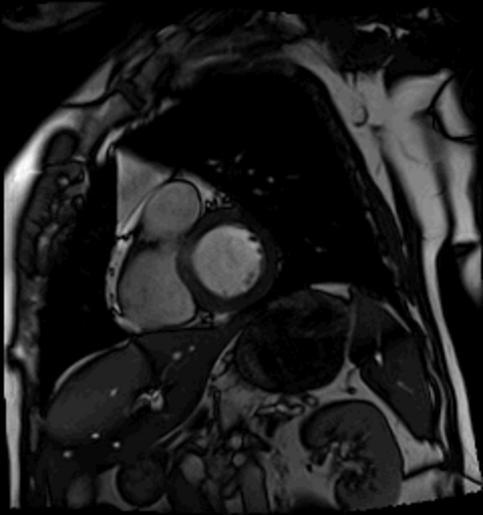

| View Original: | Multslice short axis.gif (240x256) | |||

| Keywords: Multslice short axis.gif Movie GIF format of a beating heart obtain using a 3T MRI scanner Five slices through the hear in short axis views G D Clarke 2007-05-24 G D Clarke This is an image of me obtained and owned by me Magnetic resonance imaging of the heart Animated GIF | ||||